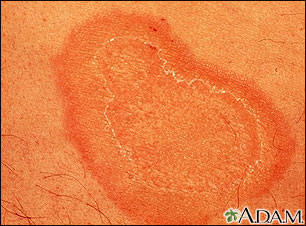

- Psoriasis -- Tends to occur as red, scaly, patches over joints and along the scalp. It is sometimes itchy. Fingernails may also be affected.